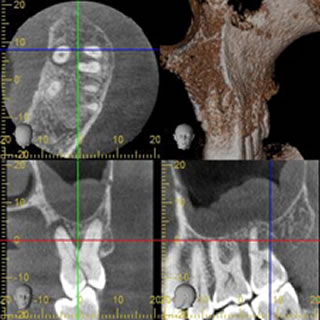

これまでの歯科臨床はレントゲン撮影により診断を行う事が通常でした。単純なレントゲン撮影では3次元の構造を2次元に押し付けているような物で、わからない部分が多く存在しました。

歯科用CTの出現により、3次元での解析が可能となり、従来の2次元のレントゲンではわからなかった病態を把握できるようになりました。圧倒的な情報量があります。